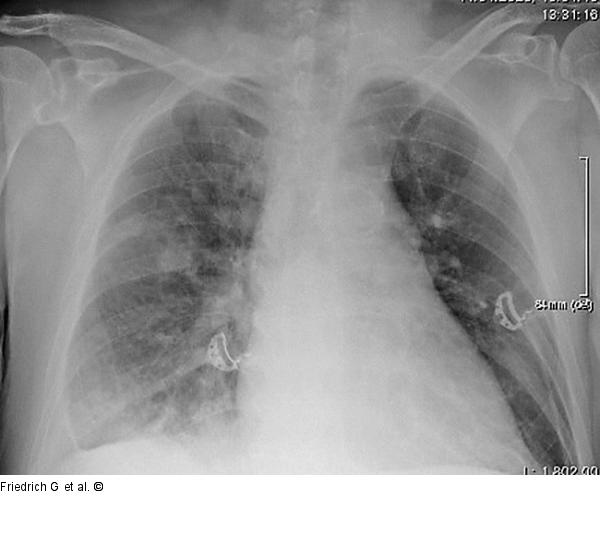

Abbildung 2: Thoraxröntgen Thoraxröntgen am Aufnahmetag |